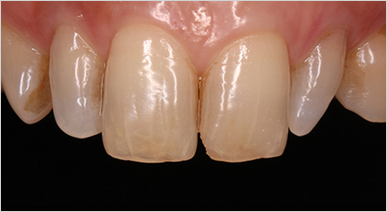

치아에 금가있고 틀어진 앞니 미니쉬 치료한 케이스

아랫니 잇몸부위 심하게 패인 치아 미니쉬 치료한 케이스

변색되고 충치 있는 앞니 미니쉬 치료한 케이스

치아 사이에 공간 있고 이전에 받았던 레진 치료 파절되어 앞니 미니쉬 치료한 케이스

* 미니쉬 시술 시 개인에 따라 부작용이 발생할 수 있습니다. * 개인의 구강 및 치아상태에 따라 치료방법과 수가가 변동될 수 있습니다. * 해당 사례는 의료법 제56조2항을 준수하여 작성되었습니다. * 본원에서 진료받은 환자이며 전후 사진의 인물이 동일인임을 밝힙니다.